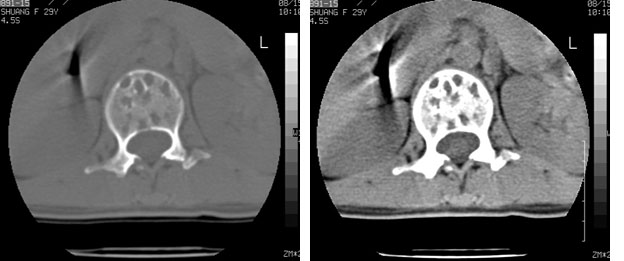

车祸致t12压缩性骨折,行ct扫描意外发现椎体多发肿瘤样病变,建议加拍骨盆平片,患者平常无症状。

考虑多发骨髓瘤可能性大。(骨松质内弥漫性分布,边缘清晰的溶骨性破坏,无硬化。睥脏增大,其内有多个圆形底密度影。淋巴瘤不除。

脾脏及椎体多发占位病变。首先考虑淋巴瘤,其次骨髓瘤。建议查本周氏蛋白

椎体多发性溶骨性破坏,部分融合,椎旁无软组织肿块、椎间隙正常,t12 压缩,脾脏增大,其内示多发低密度影,首先考虑多发性骨髓瘤。病人较年轻,平素无异常,转移瘤可能性小。